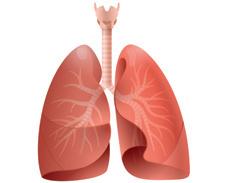

Die Lunge

Die Schleimschichten und Flimmerhärchen in der Luftröhre und in den Bronchien bringen eingeatmete Fremdstoffe wie Staub oder Rauch in Richtung Mundhöhle. Durch Husten werden sie mit Schleim aus der Lunge entfernt. Beim Ausatmen wird Kohlenstoffdioxid aus dem Körper entfernt.

• Bei einem neugeborenen Baby ist die Lunge rosafarben. Je älter ein Mensch wird, desto dunkler wird seine Lunge.

• An einem Tag atmet ein Mensch im Durchschnitt 24 000-mal. Das sind in 70 Jahren ungefähr 600 Millionen Atemzüge.